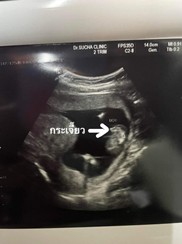

กำหนดคลอด 14 พ.ค.66 ค่ะ รู้เพศตั้งแต่ 16 weeks เพราะไปพบคุณหมอเมื่อไรก็อ้าขาโชว์ช้างน้อยตลอดเลยค่ะ

ผช ค้าบบ กำหนดคลอด19/5/23 หมอว่าเห็นเพศไวตั้งแต่ 15 5w เลยงับ จู๋โผล่มาก่อนเพื่อนเลย👶🏻💖

บ้านนี้เห็นตั้งแต่12วีคเห็นจู๋🤣 อาทิตย์ก่อนไปซาวด์15+5 จู๋ใหญ่กว่าเดิมชัดมากทค่ะ🤣

ของเราซาวด์ตอน 15 w จู๋โผล่เลยค่ะตอนนี้ผมได้ 35+4 w แล้วครับใกล้ได้ออกมาลืมตาดูโลกแล้ว